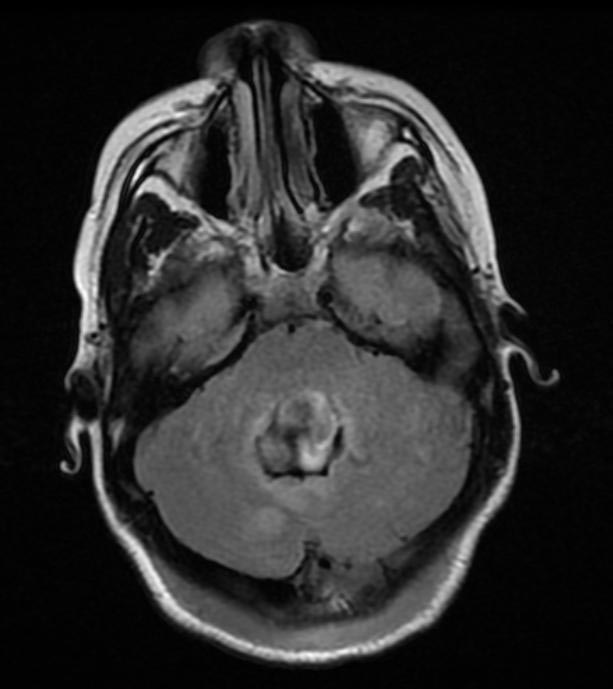

Медуллобластома лечение

Медуллобластома лечение 115 фото